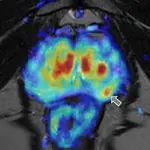

Bailer y su equipo han conseguido mejorar los métodos de ingeniería genética utilizados para manipular los virus del herpes, lo que les permite incorporar un control de destino. «Esto garantiza que nuestros virus entren en las células cancerosas cuando los inyectamos directamente en el tumor, en lugar de en las sanas. Entonces se multiplican y hacen que las células estallen», detalla el investigador principal. Este proceso libera marcadores tumorales que permiten al propio sistema inmunitario del organismo combatir el cáncer. «Además, activamos la respuesta inmunitaria con proteínas específicas que nuestros virus liberan cuando se reproducen. El sistema inmunitario reconoce entonces las células tumorales y las elimina», detalla el científico.

El equipo de investigación realizó las primeras pruebas preclínicas diseñando un virus específicamente para su uso en el tratamiento del cáncer de pulmón no microcítico. La tasa de mortalidad de este tipo de cáncer es elevada. Sólo el 22 por ciento de los pacientes femeninos y el 17 por ciento de los masculinos sobreviven a los cinco primeros años del diagnóstico de cáncer de pulmón, y el pronóstico es aún peor en el caso del carcinoma no microcítico debido a su temprana metástasis.

Los resultados de los estudios son prometedores: las células tumorales fueron eliminadas con éxito, y la inmunoterapia viral puede ser también eficaz contra las metástasis. «Tenemos que seguir explorando esto. Todavía es demasiado pronto para realizar ensayos clínicos. Sin embargo, las perspectivas a este respecto son buenas, porque el virus del herpes simple tiene otra ventaja decisiva sobre otros virus: podemos pulsar un “botón de parada de emergencia», destaca Bailer.